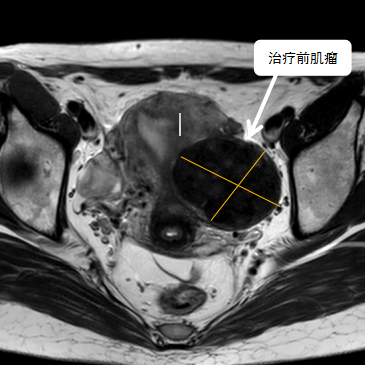

術(shù)前影像資料

經(jīng)過兩個月的藥物預(yù)處理,完善術(shù)前準備,治療當(dāng)天陳主任帶領(lǐng)團隊在3.0T磁共振清晰圖像引導(dǎo)下對子宮肌瘤進行精準消融,患者全程清醒,沒有明顯疼痛,經(jīng)過1個多小時的精細操作,手術(shù)非常成功,消融率接近90%,內(nèi)膜未見損傷!觀察一個小時后患者即自行回家。